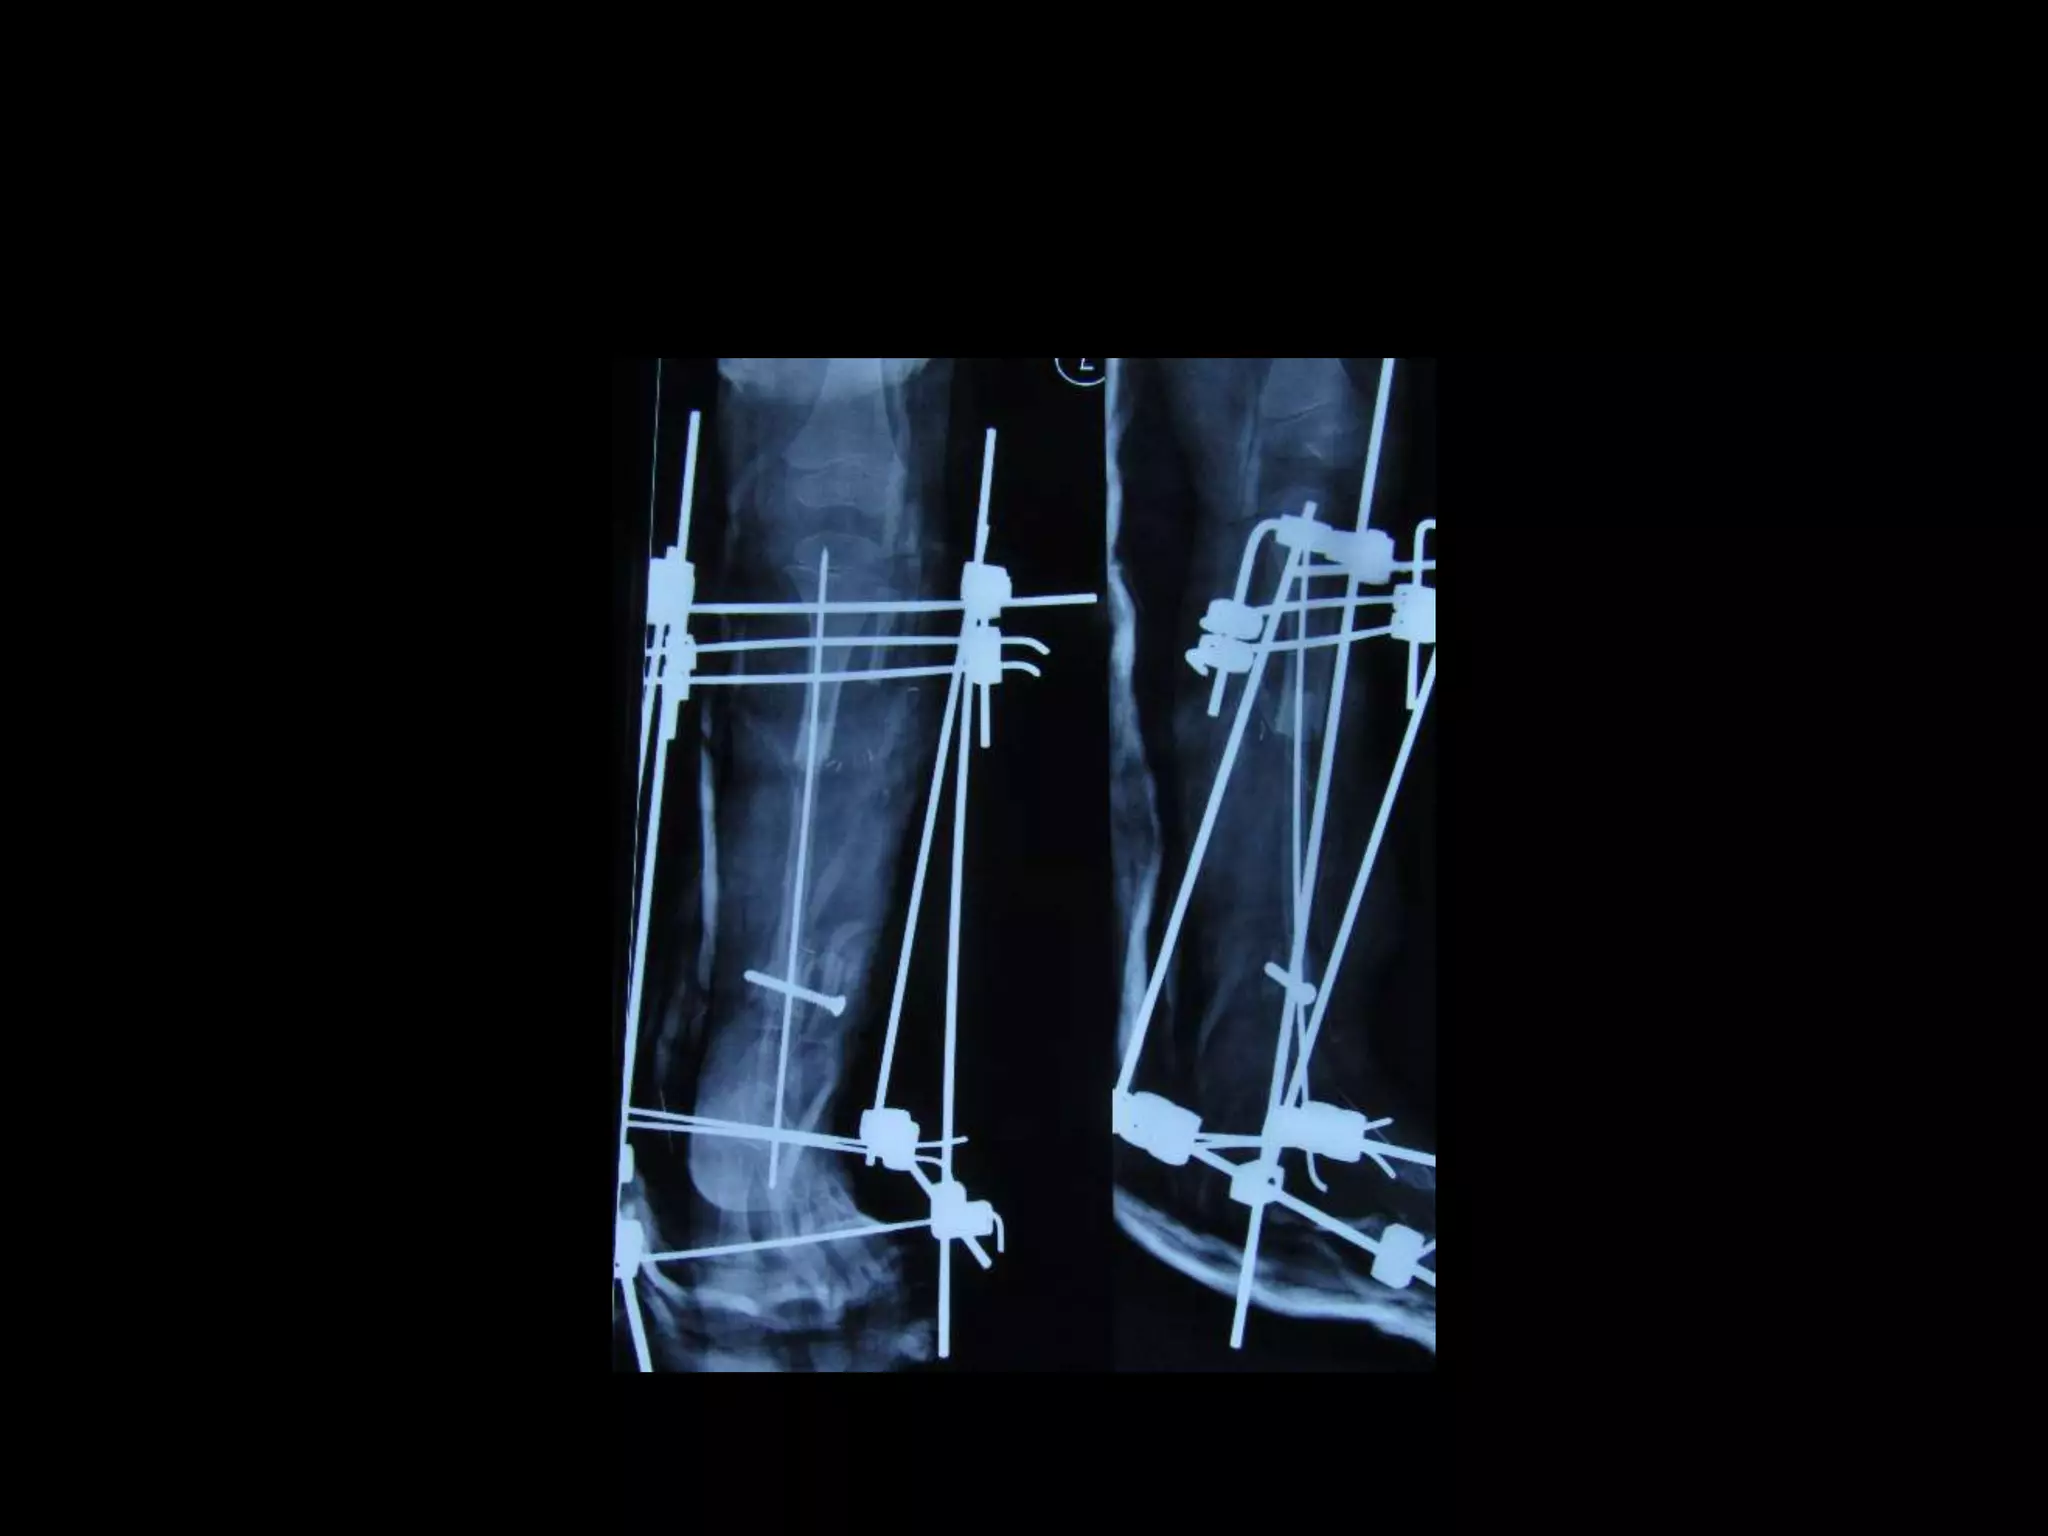

1. Vascularized fibular graft

2. External fixation

3. Intramedullary rod

4. BMP

5. Electrical stimulation

Paley X union